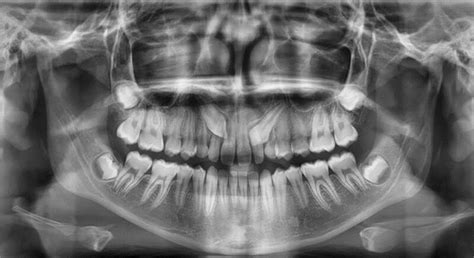

En lo que respecta a la exploración radiológica, será necesario realizar una radiografía panorámica y un TAC dental. De esa manera, el dentista podrá observar cuál es la situación del colmillo en la boca (posición, altura, inclinación…) así como su relación con los dientes vecinos.

El primer paso es el estudio en profundidad del caso. Para ello, se solicitan radiografías, como las panorámicas o tomografía computerizada (TAC); herramientas esenciales para evaluar la posición y la trayectoria de erupción de los caninos incluidos.